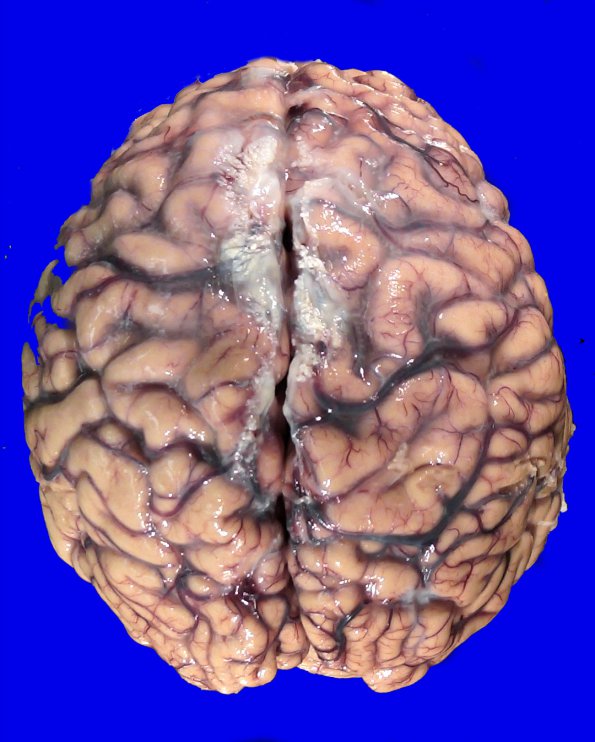

The cortical dorsal surface is only remarkable for mild sulcal expansion and cortical atrophy.